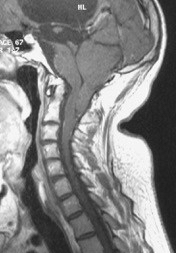

s’agissant d’une anomalie très précoce du développement, il existe des particularités notables qui différentient le Chiari 2 du Chiari 1

- le tronc cérébral est abaissé et déformé

- il s’y associe une déformation du tectum du mésencéphale

- il existe parfois un aspect dysplasique des noyaux des nerfs crâniens, responsable d’un stridor congénital (nerf vague moteur)

- la toile choroïdienne du V4 descend avec les tonsilles, parfois très bas dans le canal spinal

- la fosse postérieure est petite avec un torcular abaissé, une tente verticalisée, un hiatus tensoriel large, et un foramen occipital large